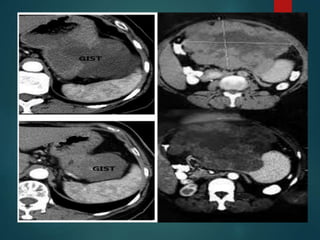

Gastrointestinal Stromal Tumor –

GIST..

• Primary small bowel tumors can extend into the

mesentery and the typical example of that is the

GIST.

• Have a large mesenteric component and very

small attachment to the bowel, that may not

appreciate it.

• On CT they are of mixed density due to necrosis

and hemorrhage and they tend to be well

vascularized, so they will enhance.

Gastrointestinal Stromal Tumor– GIST.. • Primary small bowel tumors can extend into the mesentery and the typical example of that is the GIST. • Have a large mesenteric component and very small attachment to the bowel, that may not appreciate it. • On CT they are of mixed density due to necrosis and hemorrhage and they tend to be well vascularized, so they will enhance.